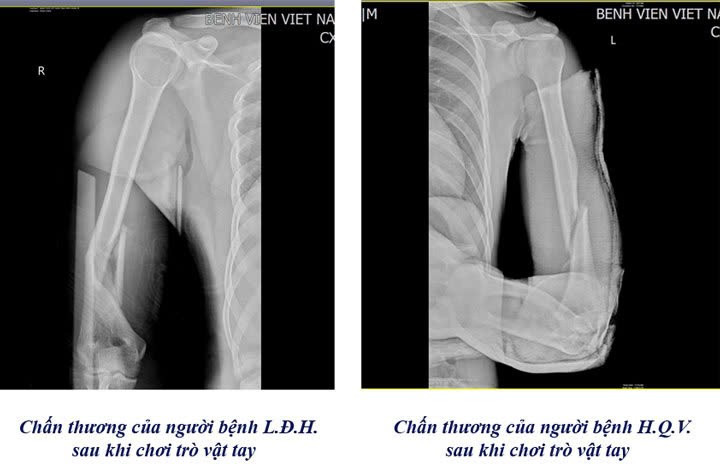

Chỉ trong vòng 1 tuần, Khoa Chấn thương Chỉnh hình & Bỏng, Bệnh viện Việt Nam – Thụy Điển Uông Bí đã tiếp nhận 3 trường hợp nhập viện do gãy xương cánh tay, nguyên nhân là từ trò chơi “vật tay”.

Theo bác sĩ Khoa Chấn thương Chỉnh hình & Bỏng cho biết, khi vật tay, lực xoay đột ngột tác động lên xương cánh tay có thể vượt ngưỡng chịu đựng, gây gãy xoắn xương cánh tay, thậm chí di lệch.

Gãy xương trên phim chụp của các bệnh nhân chơi trò vật tay - Ảnh BVCC

Cũng theo bác sĩ, bệnh viện thường xuyên tiếp nhận các trường hợp bị gãy xương cánh tay từ trò chơi “vật tay”.

Có những trường hợp nhập viện trong tình trạng gãy nham nhở, gây khó khăn cho các bác sĩ trong việc đưa các mảnh xương về vị trí ban đầu, gia tăng nguy cơ tổn thương dây thần kinh quay, dây thần kinh trụ và mạch máu lân cận. Đa phần các trường hợp nhập viện đều ở độ tuổi học sinh, sinh viên.